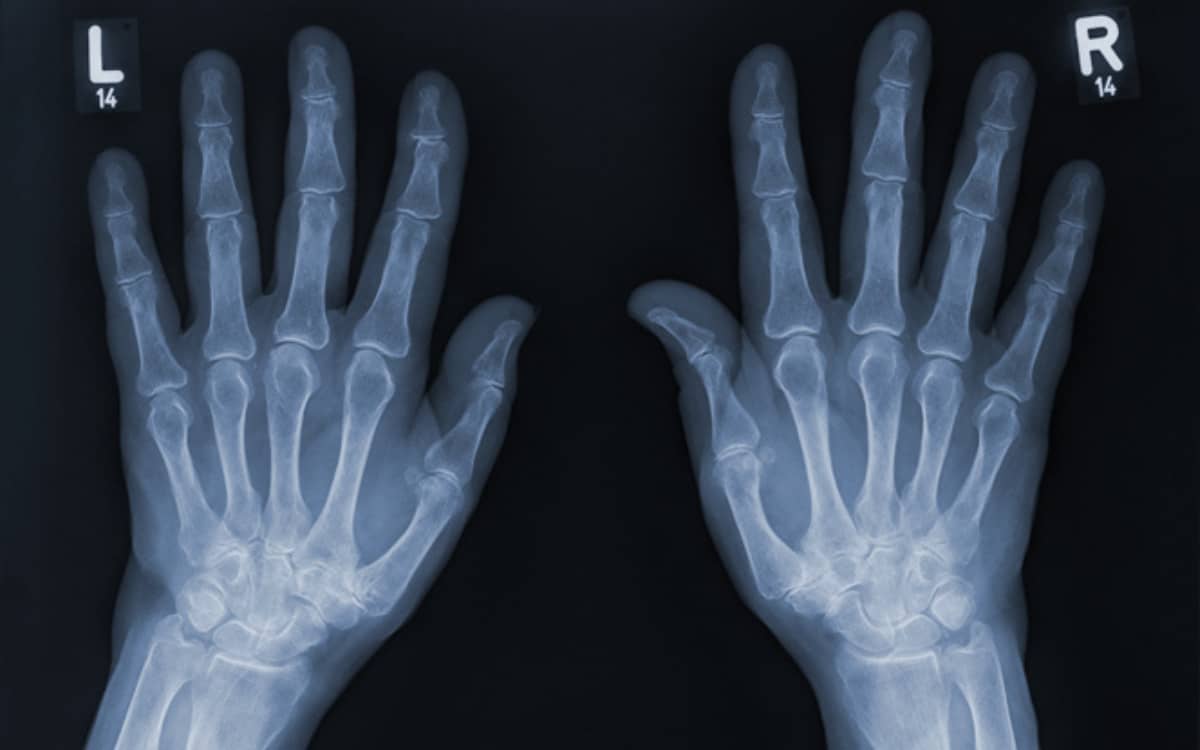

To test it further, he placed his wife Anna Bertha’s hand in front of a photographic plate.

The resulting image revealed her bones and wedding ring, a sight equal parts eerie and revolutionary.

Doctors quickly realized its medical potential, using X-rays to locate bullets, diagnose fractures, and identify swallowed objects.

Suddenly, physicians could see beneath the skin without making a single incision.

Orthopedics advanced as doctors aligned broken bones more accurately, dentistry adopted X-rays to detect cavities, and surgery became more precise.